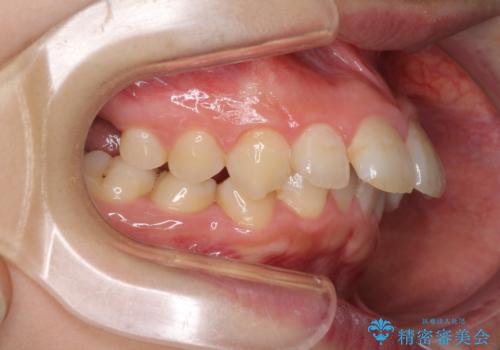

下顎は左右2番目の歯が2本欠損しており、上下前歯の前後的な位置は著しくずれている状態でした。

骨格的にも上顎骨が前突傾向にあり、極端な過蓋咬合になっていました。

強い咬合力に抵抗するように歯を動かす必要があるにもかかわらず、上顎第一大臼歯が1本欠損しているため、治療は困難を極めることが予想されました。

上顎前突を改善するために上顎左右第一小臼歯を抜歯し、補助装置を用いて上顎臼歯が前方に移動しないように工夫しながら、表側のワイヤー装置にて歯列を整えていくこととしました。